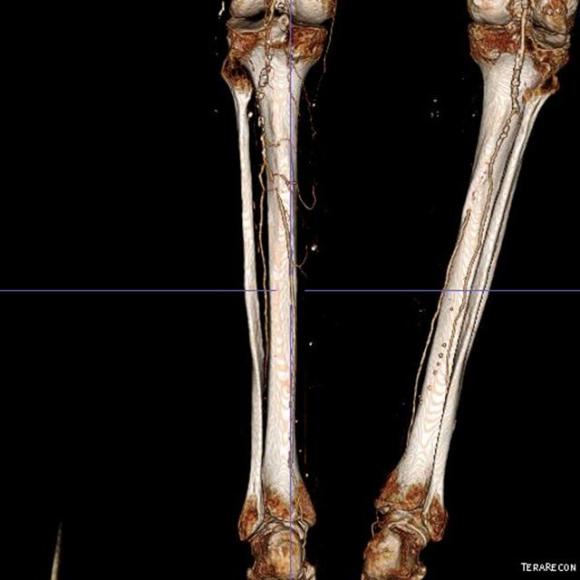

The patient is a gentleman from out of state who had called about problems he was having with walking and with leg ulcers that wouldn’t heal. He is in his seventies and has a pacemaker for an arrhythmia for which he was on Xarelto. He also had type II diabetes. He had bilateral lower extremity deep venous thromboses 6 years prior requiring IVC filter placement. The filter occluded, and it resulted in sudden sharp and debilitating pain in both legs with walking short distances -some days only 50 paces.He described it as an unbearable pain in calves and thighs that felt like his legs were going to burst. He also had ulcers on his legs that would heal with ministration but soon recur. This was all despite being quite active, with regular workouts, and being fit. He was compliant with compression. He sent a CT scan done last year (below).

It showed an Optease retrievable vena cava filter that was occluded and the iliac systems bilaterally (right above and left below) were chronically occluded with patent vena cava above and femoral confluences bilaterally below.

Examination revealed a fit and trim man in his 70’s in no apparent distress. He had bilateral leg edema that was moderate with small superficial and tender ulcers of the right posterior distal calf. Pulses were normal. He was taken to our hybrid suite and venography from femoral vein access in the proximal thigh in the supine position revealed his right and left iliac venous systems to be occluded (below figures).